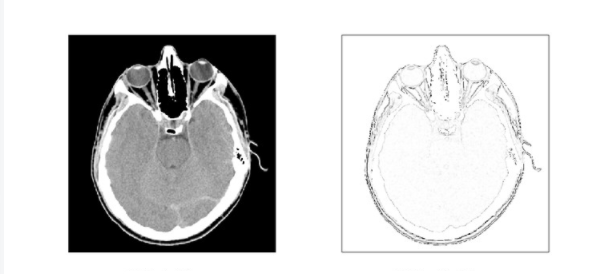

2.1 基于数学形态学的边缘检测:

数学形态学是基于积分几何和几何概论建立的关于图像形状和尺寸的研究方法,实质上是一种非线性滤波方法。数学形态学的方法应用于视觉图像的处理就是用具有一定形状、大小的结构元素去探测、度量和提取图像中对应形状,以达到对图像进行处理、分析识别的目的。在图像处理的过程中,主要使用的是二值形态学和灰度形态学。我们可以来看看这个方法对于图像轮廓的提取能力如何:

2.2 基于小波和小波包变换的边缘检测算法:

小波变换具有非常丰富的数学理论做支撑,有着非常大的发展前景;小波变换很好的利用了时域频域的局部化特征,通过对信号进行细化分析,能达到高频处时间细分、低频处频率细分,所以小波变换适合复杂图像的边缘检测,它的边缘处理能力如下:

2.3 基于模糊理论的边缘检测算法:

实际应用中的图像边缘是不确定的,具有模糊性,用经典数学描述不准确,所以利用模糊理论进行边缘检测时,首先将图像看作是一个模糊集,将图像中每一个具有特定灰度级的元素进行标记,从而将待处理的图像映射为具有模糊特征的矩阵,在此基础上进行模糊增强处理,由于图像边缘梯度的模糊性,这个方法能够得到比较好的边缘检测效果。下图就是模糊方法处理后得到的图像边缘:

2.4 基于神经网络的边缘检测算法:

神经网络是一种基于现有数据创建预测的计算系统,随着神经网络技术的发展,人们又将其加入到图像边缘检测中,希望能够获得更好的检测结果。神经网络的边缘检测一般利用 BP 网络,采用滚动训练和权值随机扰动方法,提高了神经网络的学习效果,获得的边缘图像封闭性好,更加精确。我们来看看它实际的处理能力: